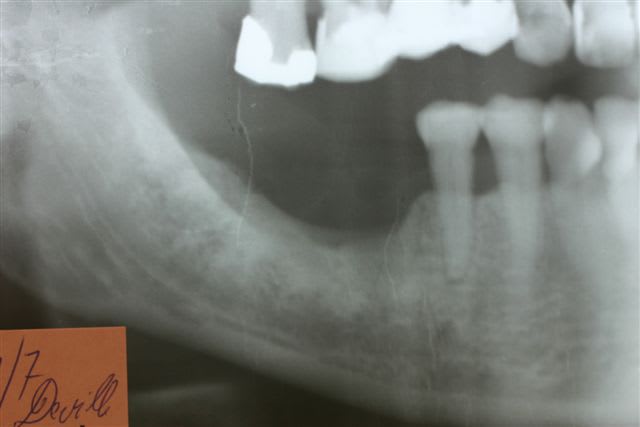

1er cas : une patiente qui perd trois implants sur 4 en zone 47 46 37 36... Elle m apporte son dentascan avec les implants en place en train de foirer

Que voit on ???

1. des implants posés bcp trop lingual ds un os très blanc donc très cortical avec une médullaire rare

2. implants courts de gros diamètre avec macrospires très agressives

3. aucune préparation du site par ostéotension

4. pas d arrêt tabagique demandé

5. après intégration pose de couronnes définitives céramiques en unitaire

Elle est arrivée avec les implants explusés depuis plusieurs mois

Un seul avait pris donc bon signe on peut y retourner

Son prat lui avait posé un bridge 34 35 extension distale 36

Secteur 40 : je lui ai posé deux monodisk en enfoui parfaitement pris et tjs équipé de leur dents provisoires métal résine depuis 5 ans

Le cas 2 c est pour plus tard car un peu plus long à expliquer mais làa ça commençait par un échec de greffe avec de l iliaque pour remplacer 47 46